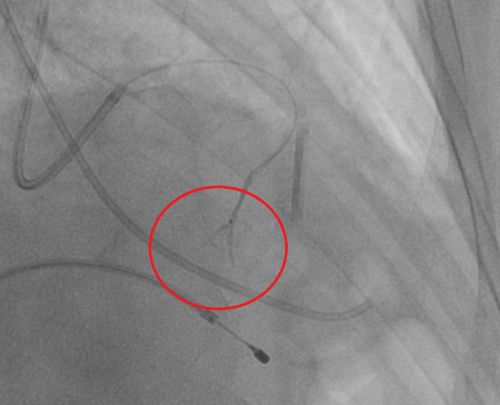

使用微粒球对间隔支进行栓塞。